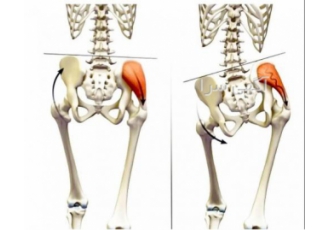

حرکات اصلاحی جهت رفع ناهنجاری های اسکلتی عضلانی